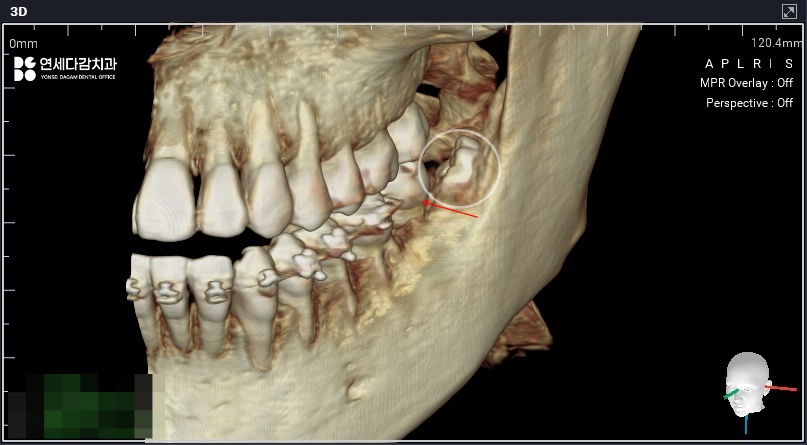

더불어, 아래쪽 매복 어금니 같은 경우

치근단 하방 하치조신경관과 근접할 때가 많아

사전에 정확한 거리 관계를 파악합니다.

자칫해서 진료 도중 자극을 줄 수 있으며

일시적으로 감각 마비 같은 후유증이 남을 수 있고

드물게는 영구적으로 남는 사례도 있습니다.

2026.01.06

따라서 안전한 각도와 접근 경로를

충분히 고려한 진료 계획 수립이 필수입니다.

이 과정에서 치배 조직이 함께 확인되는 경우

가능한 제거와 동시에 병리학적 검사를

의뢰하는 것도 바람직합니다.

치배는 대부분 생리적인 조직 중 하나이지만,

드물게는 치성 낭종이나 악성 종양이 될 수 있으니

의심 소견이 있는 경우 분석을 병행하는 것도

안전하고 책임감 있는 진료 과정이라 할 수 있습니다.

2026.01.27

가락동 치과 에서 확인해 본 결과

과형성된 치배로 결론이 나왔으며,